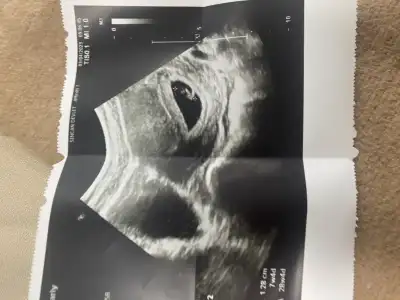

Karından ultrason muydu cnm?Kızlar merhaba 10 haftalık hamileyim. Keseye göre cinsiyet tahmini yapabilir misiniz? Yuvarlak kese kız, uzun muz gibi olan kese erkek olur diyorlar. Benimki nasıl sizce? Çok çok heyecanlıyım

İlk halini de ekledim :)